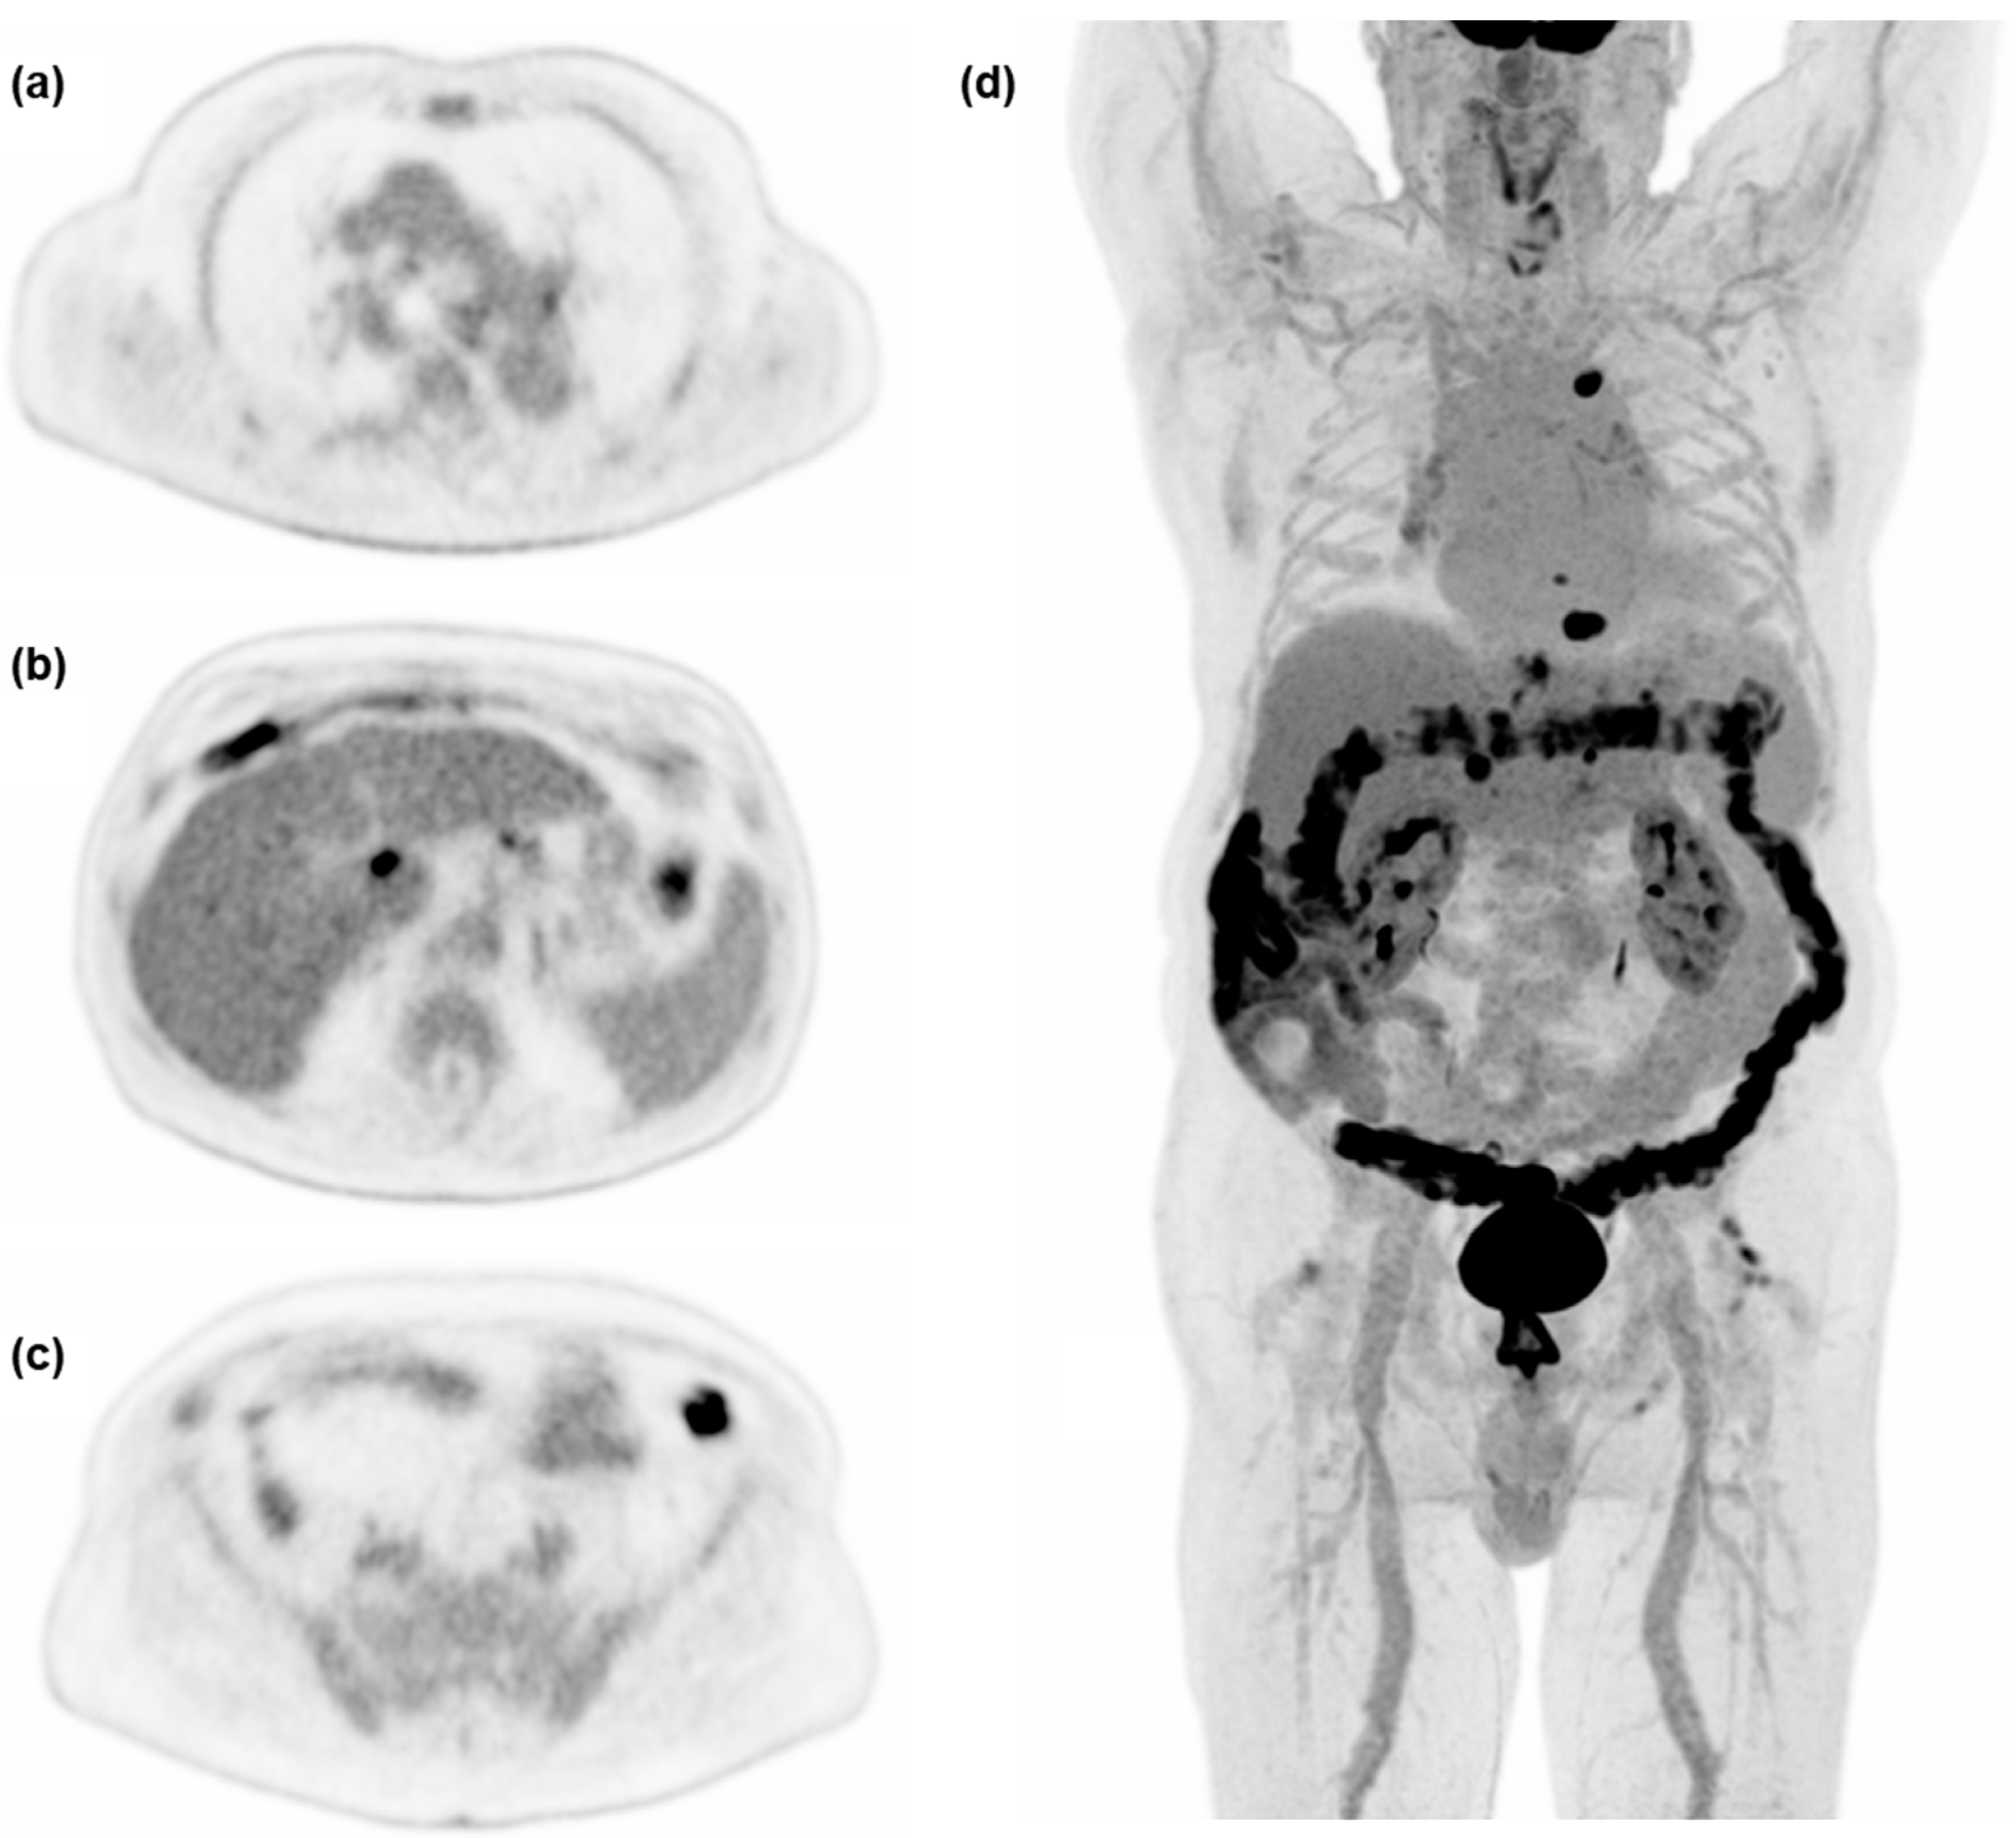

3.3. Image Quality

3.4. Lesion Detection